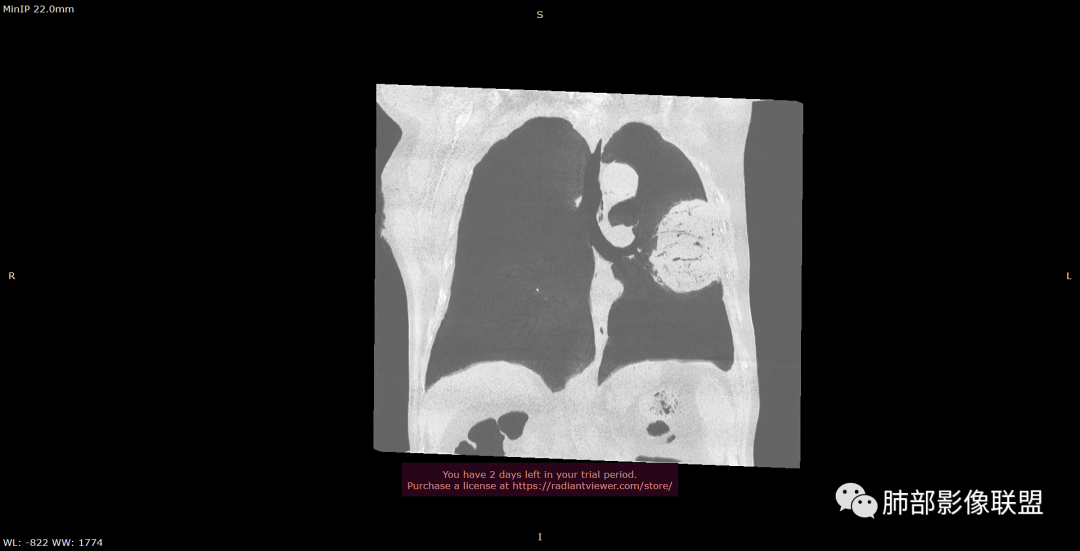

左肺上叶大肿块,膨胀性生长,边界清,密度较低,见部分坏死区,强化弱,肿块见支气管充气V扩张征,分布僵直,枯树枝特点,另一个重要特点血管造影征,淋巴瘤,肿块长轴与胸膜平行,与隐球菌鉴别,隐球荚膜抗原检查,明确诊断经皮肺穿刺。另胸膜钙化(问诊既往有无患胸膜炎病史)。

左肺上叶胸膜下肿块,宽基底与胸膜相连,跨叶裂,边缘清晰膨隆,其内支气管充气,部分扩张、僵直,无明显强化,血管造影征,考虑淋巴瘤,鉴别腺癌

左肺胸膜下巨大占位,跨叶裂,宽基底与胸膜相连,胸膜钙化,平扫密度较低,强化不明显,可见内部血管显影,支气管充气征和扩张,考虑为恶性,倾向于淋巴瘤

左侧胸腔巨大肿块,跨叶生长,临近胸膜钙化,边缘模糊,可见支气管影,定位肺内,增强后轻度强化,边缘见血管影,考虑淋巴瘤,鉴别肉瘤

左肺上叶胸膜下肿块,膨胀性生长,边界清晰,密度不均部分坏死,未见强化,病灶内支气管迂曲扩张,病灶长轴与胸膜平行,胸膜下脂肪间隙存在,胸膜钙化,考虑放线菌?毛霉?鉴别淋巴瘤

支持淋巴瘤,左上肺大肿块,有分叶,边缘光整,病灶内密度不均,可见支气管扩张征,增强后可见血管影征。周围肺野清晰。

左肺上叶肿块,宽基底与胸膜相连,跨叶裂,边缘清晰膨隆,可见小分叶,其内支气管充气,部分扩张、僵直,呈枯枝征,支气管达边征,增强无明显强化,可见血管造影征,考虑恶性病变,淋巴瘤,鉴别粘液腺癌。

大肿块,边缘光滑,深分叶

近端支气管堵塞、推移为主

部分类似于脐凹征

内部支气管扩张

肺动脉推移为主,边缘部分进入